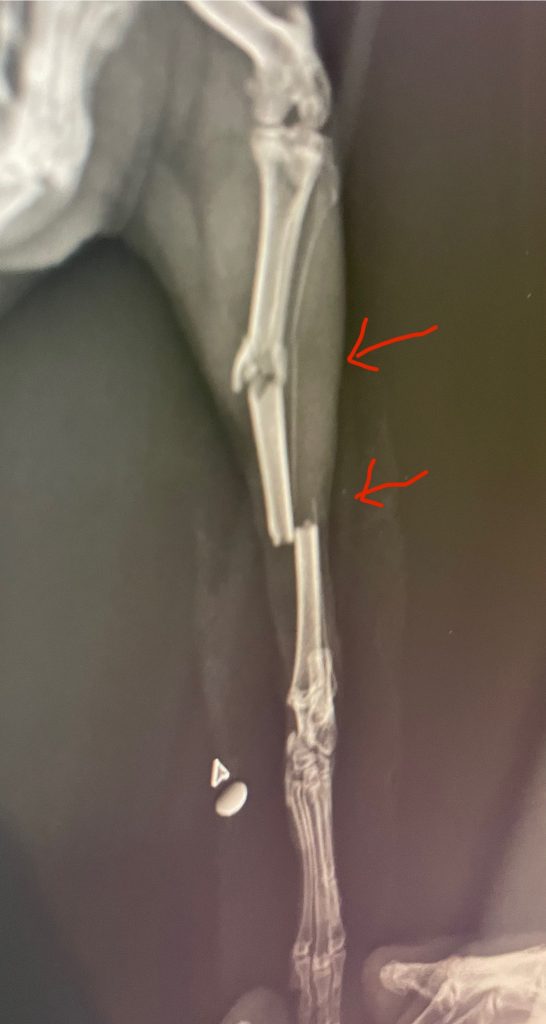

まだ若く、複数個所での骨折をみとめたため、飼い主様とご相談し手術を行いました。

創外固定と髄内ピンを組み合わせた方法です。本当はもう少し創外固定のピンを多く入れたかったですが骨の細さ、骨折の位置からこの本数が限界と判断しました。

2か月でしっかりくっついてくれたので抜ピンしました。